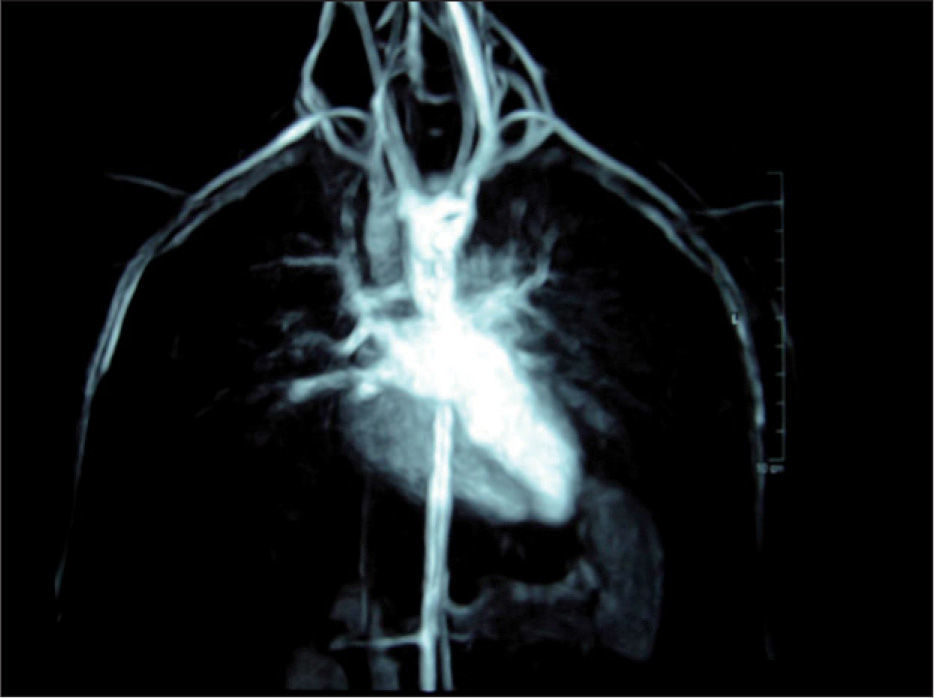

Anillo vascular MedlinePlus enciclopedia m dica illustraci n best sale, Anillos vasculares best sale, Anillos vasculares best sale, Anillo vascular. Web de las cardiopat as Cong nitas best sale, Anillos vasculares best sale, Anillos vasculares best sale, Caracter sticas y manifestaciones cl nicas de los anillos best sale, Anillos vasculares best sale, ANILLOS VASCULARES EN PEDIATR A. PRESENTACI N DE 2 CASOS best sale, Anillos vasculares best sale, Figure 1 from Anillo vascular por doble arco a rtico sim trico best sale, Anillos vasculares Radiolog a PPT best sale, Caso cl nico. Anillos Vasculares best sale, Anillo vascular por doble arco a rtico sim trico. Reporte de un caso best sale, PDF Anillo vascular completo diagn stico prenatal de doble arco best sale, VASCULAR RINGS MAGNETIC RESONANCE FINDINGS best sale, Anillos Vasculares y Slings PDF PDF Aorta Tos best sale, PDF S ndrome de Rubinstein Taybi asociado a anillo vascular best sale, Anillo vascular 15 anos de experiencia en el Hospital Infantil de best sale, Diagn stico y tratamiento de persistencia de cuarto arco a rtico best sale, Anillo vascular por doble arco a rtico sim trico. Reporte de un caso best sale, Reparaci n de sling de la arteria pulmonar sin necesidad de bypass best sale, PDF Anillos vasculares obstrucci n de v a a rea en ni os. Serie best sale, Figure 2 from Anillo vascular por doble arco a rtico sim trico best sale, Anillo vascular 15 anos de experiencia en el Hospital Infantil de best sale, Anillos vasculares completos Anales de Pediatr a best sale, ANILLOS VASCULARES HALLAZGOS POR RESONANCIA MAGN TICA best sale, Los Anillos vasculares Una amenaza creciente para la v a best sale, Anillo vascular por doble arco a rtico sim trico. Reporte de un caso best sale, Vascular rings and pulmonary arterial sling from respiratory best sale, Anillos vasculares nuestra experiencia en 18 casos best sale, Anillo vascular. Diagn stico por ecocardiograf a en periodo fetal best sale, Anillo vascular por doble arco a rtico sim trico. Reporte de un caso best sale, Figure 2 from Anillo vascular por doble arco a rtico sim trico best sale, Anillos vasculares y compresi n traqueo esof gica 15 a os de best sale, Figure 1 from Anillo vascular por doble arco a rtico sim trico best sale, Doble arco a rtico. Reporte y an lisis de caso en un paciente best sale, S ndrome de Rubinstein Taybi asociado a anillo vascular completo best sale, Multidetector Computed Tomography for Congenital Anomalies of the best sale, PDF Anillos vasculares como diagn stico diferencial del asma best sale, Anillos vasculares nuestra experiencia en 18 casos best sale, Anillos Vasculares y Slings PDF PDF Aorta Tos best sale, Vascular Rings Practice Essentials Anatomy Pathophysiology best sale, Multidetector Computed Tomography for Congenital Anomalies of the best sale, Resumen topografia miembro inferior Anatom a e Im genes best sale, Vascular Rings Practice Essentials Anatomy Pathophysiology best sale, Cardiopat as cong nitas. Anillo vascular best sale, Anillos vasculares completos Anales de Pediatr a best sale, Anillos vasculares y compresi n traqueo esof gica 15 a os de best sale, Multidetector Computed Tomography for Congenital Anomalies of the best sale.